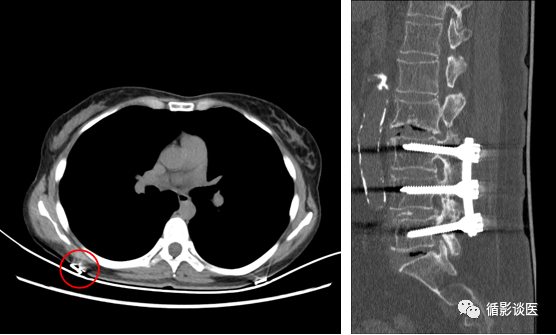

如图:左图红圈内患者所穿衣物上明显有高密度异物,但并不影响肺内影像。右图椎体内钢钉也并不影响其它椎体显示。